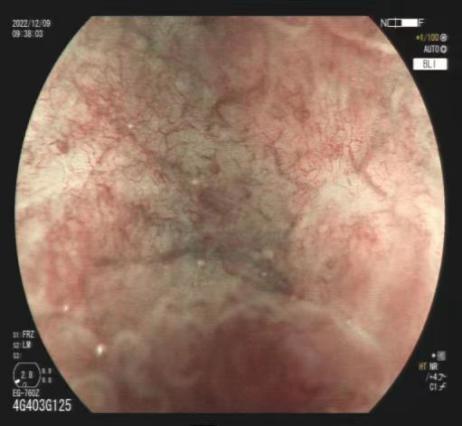

2.激光放大染色内镜

微米级病灶识别率提升40%,早癌检出率全区领先。

放大内镜下可见不规则微结构 BLI模式下可见不规则微血管